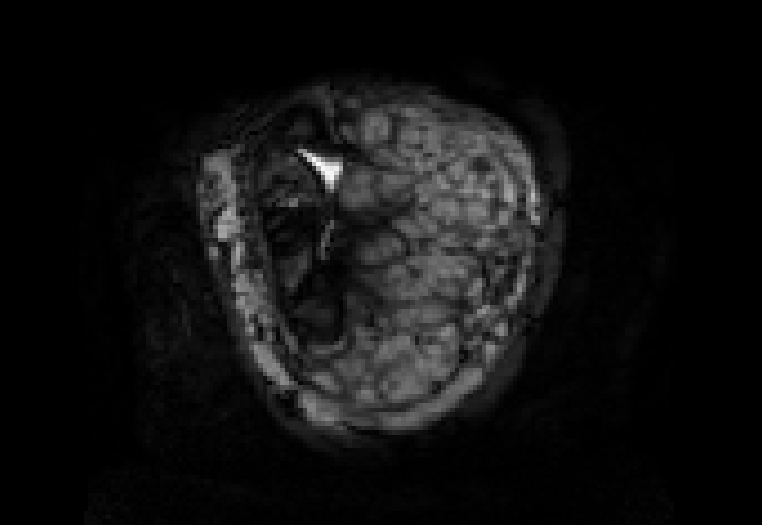

This atlas and the linked publication [1] aim to give a visual overview over T2-weighted anatomical imaging and T2* relaxometry placental data. Both have been widely used in the last years to assess placental structure and function in-vivo [2-10].

Data from healthy controls is displayed over GA, different acquisition choices and possible dynamic effects are depicted and placentae from different cohorts affected by complications are shown.

Display description: All placentae are shown in maternal coronal plane (See A). The slice with the largest placental volume was chosen. The same colormap was chosen for all placentae (See B).